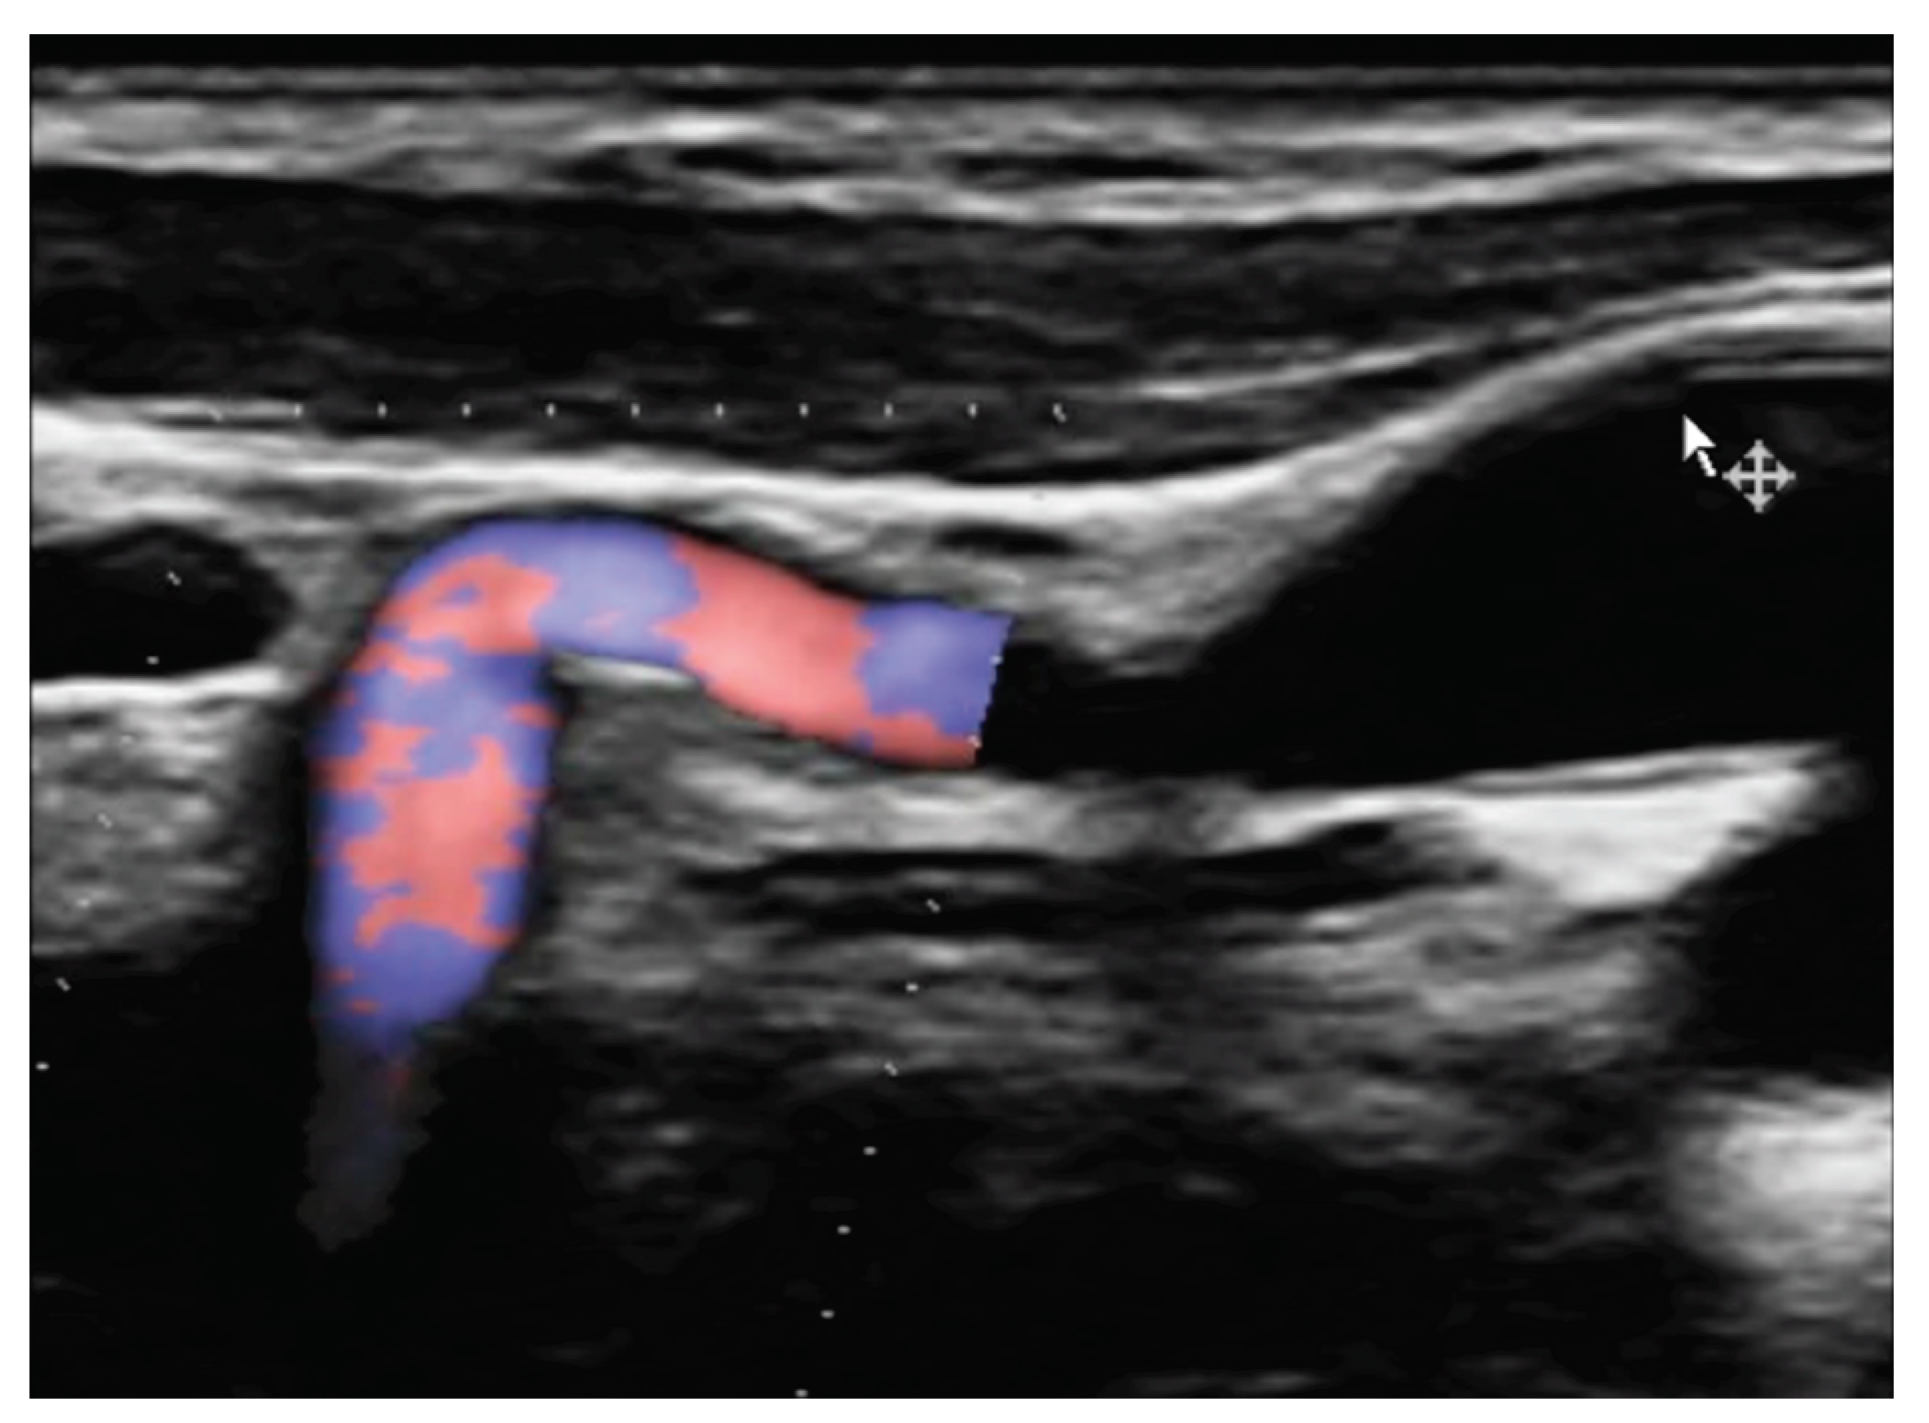

Since the advent of endovascular procedures, the histopathological classification has been replaced by an angiographic classification: focal or multifocal FMD. Multifocal FMD alternates areas of stenosis and dilation (“string of beads”) and is usually located in the mid and distal portion of the artery [147,148]. Recently, aneurysm, dissection, and arterial tortuosity have been included in the phenotype of FMD. However, a diagnosis of FAD cannot be established in the absence of focal or multifocal stenosis. Tortuosities can also be seen in the carotid, vertebral, and renal arteries. Tortuosity of the mid to distal portion of the internal carotid artery (ICA) may lead to an “S-curve”. The S curve is not specific for FMD, but its presence in individuals <70 years of age should alert the clinician [147]. Figure 1 and Figure 2.

Headaches are the most frequent, but non-specific symptoms (50-70% of patients with FMD) [147,151]. Pulsatile tintinnus may be associated with cervical artery dissection. The prevalence of cervical artery dissection and intracranial saccular aneurysm is higher among patients with FMD, with a higher rate of neurological complications (TIA, ischemic stroke, subarachnoid hemorrhage). Figure 3

The risk of long-term progression of FMD and the occurrence of aneurysm and dissection are not well-known [148]. CTA and MRA are the initial imaging modalities. Catheter-based angiography must be reserved for cases that may require intervention. Carotid DUS maybe useful for surveillance, but with some drawbacks: unsatisfactory access to vertebral and carotid arteries (especially the distal cervical portion of the ICA and intracranial arteries), no validated criteria for FMD [147]. Figure 4 and Figure 5